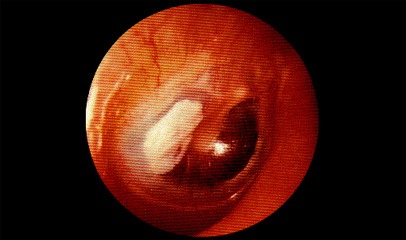

Основным симптомом тимпаносклероза является стойкая тугоухость при отсутствии гноетечения из уха. Отоскопическая картина обычно характеризуется наличием в барабанной перепонке обширного перфоративного отверстия с утолщенными краями, через которое иногда можно увидеть типичные для тимпаносклероза наслоения, в ряде случаев имеется обширный атрофический рубец. Наиболее достоверно проявления тимпаносклероза могут быть обнаружены с помощью операционного микроскопа.

Тональная пороговая аудиометрия - смешанная тугоухость с преобладанием кондуктивного компонента, так как высокие пороги слуха при костном звукопроведении наблюдаются редко. Отоскопия - рубцовые изменения барабанной перепонки. В отличие от петрификатов тимпаносклеротические бляшки всегда интимно связаны с рукояткой молоточка.